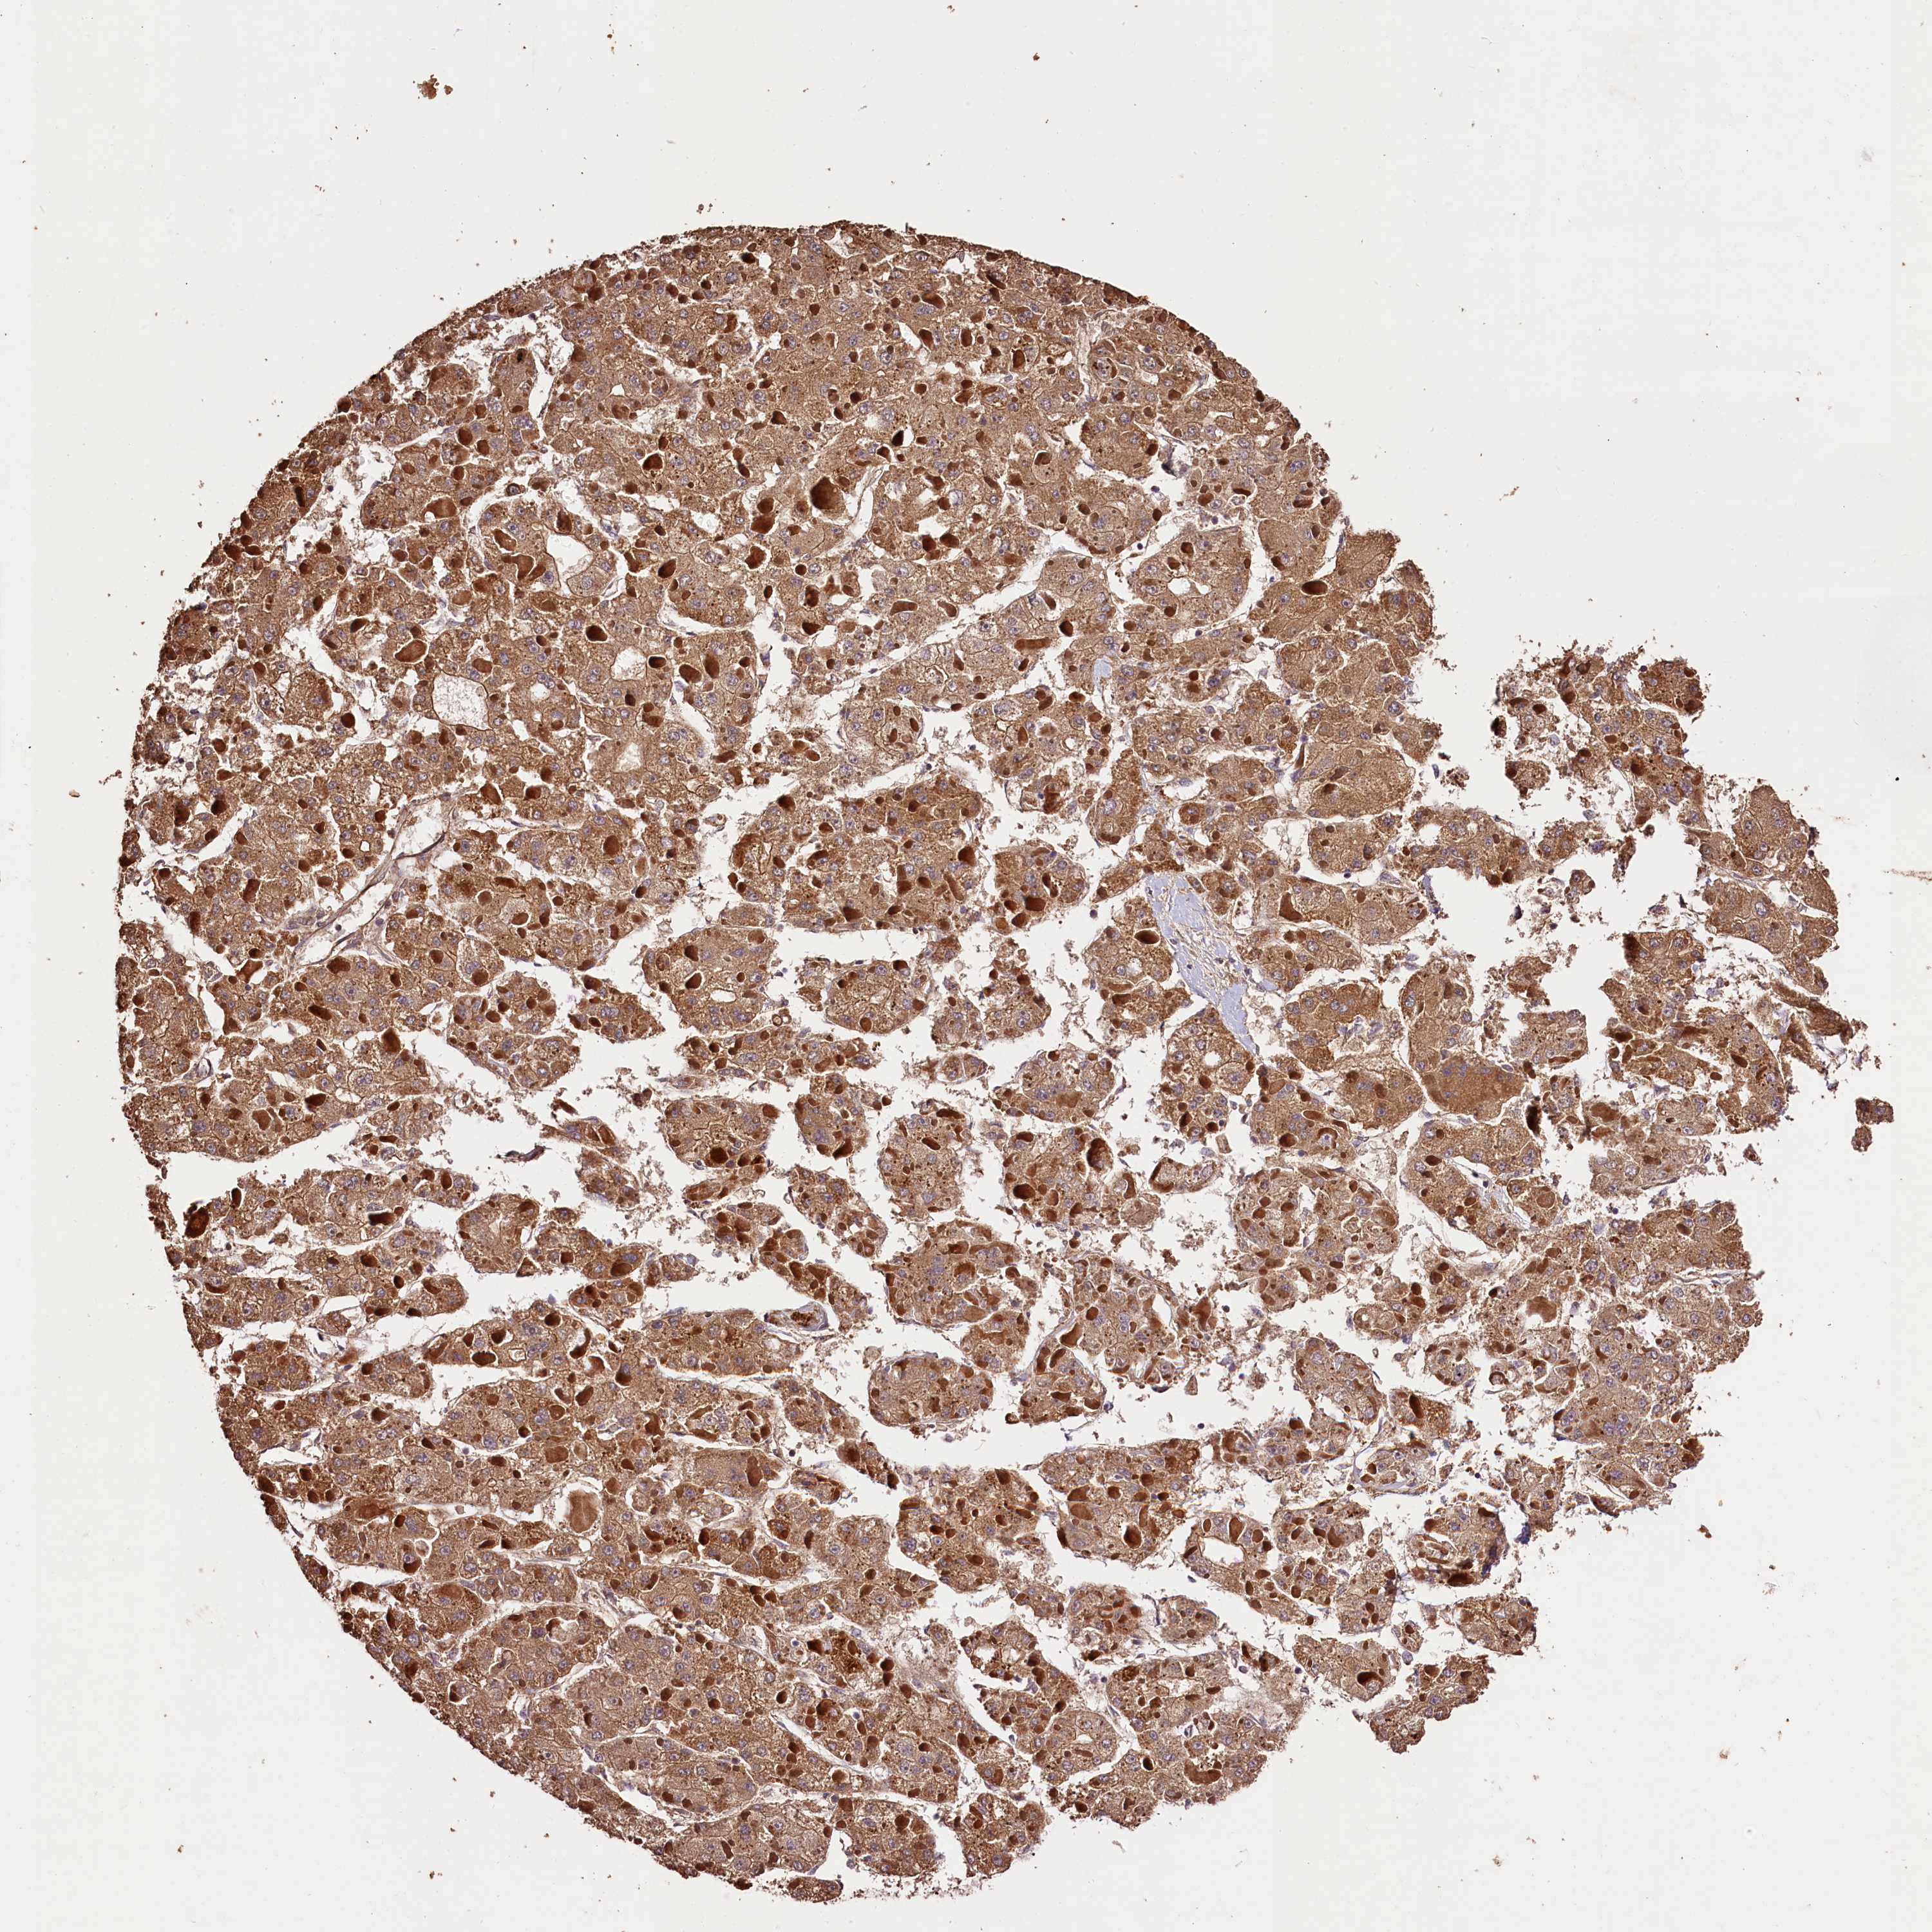

LIVER CANCER - Protein expressioni

A mouse-over function shows sample information and annotation data. Click on an image to view it in a full screen mode. Samples can be filtered based on level of antibody staining by selecting one or several of the following categories: high, medium, low and not detected. The assay and annotation is described here.

Note that samples used for immunohistochemistry by the Human Protein Atlas do not correspond to samples in the TCGA dataset.

Antibody stainingi

Antibody staining in the annotated cell types in the current human tissue is reported as not detected, low, medium, or high, based on conventional immunohistochemistry profiling in selected tissues. This score is based on the combination of the staining intensity and fraction of stained cells.

Each image is clickable and will lead to virtual microscopy that enables deeper exploration of all samples and also displays staining intensity scores, fraction scores and subcellular localization as well as patient and tissue information for each sample.

Antibody HPA041008

Antibody HPA041307

Staining

High

Medium

Low

Not detected

Intensity

Strong

Moderate

Weak

Negative

Quantity

>75%

75%-25%

<25%

None

Location

Nuclear

Cytoplasmic/membranous

Cytoplasmic/membranous,nuclear

Cholangiocarcinoma

Carcinoma, Hepatocellular, NOS